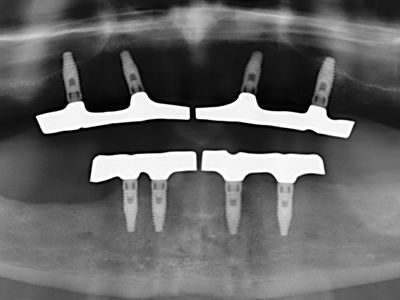

Indication: Sinus lift

Preparation of the lateral window during an external sinus floor elevation is challenging, particularly for implantologists with little surgical experience. Removal of the bone cover of the sinus without injuring the underlying Schneiderian membrane is only part of the operation – after establishing an adequate access, the membranous lining of the sinus must be carefully mobilized to make space for the augmentation materials or the implants. Piezo surgery is useful for this indication in two ways: diamond-coated instruments can be used for selective bone ablation and the underlying mucous membrane remains intact when the procedure is done carefully. The ultrasonic frequencies also enable detachment of the mucous membrane without complications – the frequencies are transmitted into the space between the mucous membrane and sinus floor by special blunt attachments (Cassetta, Ricci et al. 2012, Pereira, Gealh et al. 2014) (Rickert, Vissink et al. 2013). As a result, it is not surprising that current reviews of external sinus floor elevation positively evaluate the use of piezoelectric devices as well as the use of roughened implant surfaces and bone replacement materials (Wallace, Tarnow et al. 2012).